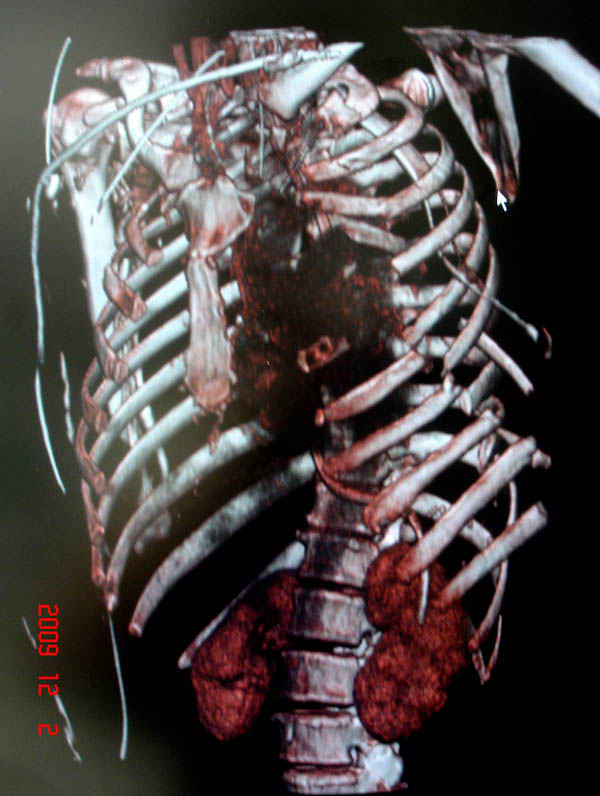

К нам поступила больная 56 лет после автоаварии в бессознательном состоянии, которая срочно заинтубирована в приемном отделении и сделаны необходимые исследования. Данные КТ и рентген показали перелом дистального бедра и Dissociation upper extremity - закрытый отрыв левой верхней конечности на уровне грудинно-ключичного сочленения и множественные переломы ребер.

На поверхности грудной клетки из-за полного разрыва грудной мышцы под кожей заметно биение сердца и след от ремня безопасности. Грудная клетка расширена из-за смещения верхней конечности вверх и латерально. Признаков васкулярного повреждения нет, и из-за отсутствия сознания не смогли определить наличия повреждения нервов.

На седьмые сутки нами совместно с торакальным хирургом сделана операция по фиксации грудинно-ключичного сочленения и переломов ребер.

После кожного разреза обнаружили полный разрыв грудной мышцы и повреждение перикард от уровня второго до восьмого ребер. Хирург находился с нами и после нашей работы зафиксировал повреждение перикарда и разрыв грудной мышцы.